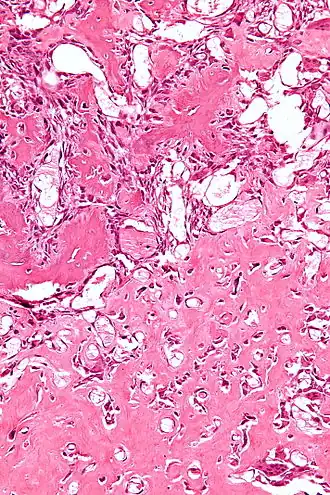

Vue histologique d'un ostéoblastome.

Histologiquement, les ostéoblastomes sont similaires aux ostéomes ostéoïdes, produisant de l'os au milieu du tissu conjonctif fibro-vasculaire. L'ostéoblastome peut atteindre plus de 2,0 cm de diamètre alors que les ostéomes ostéoïdes ne dépassent pas 2 cm.